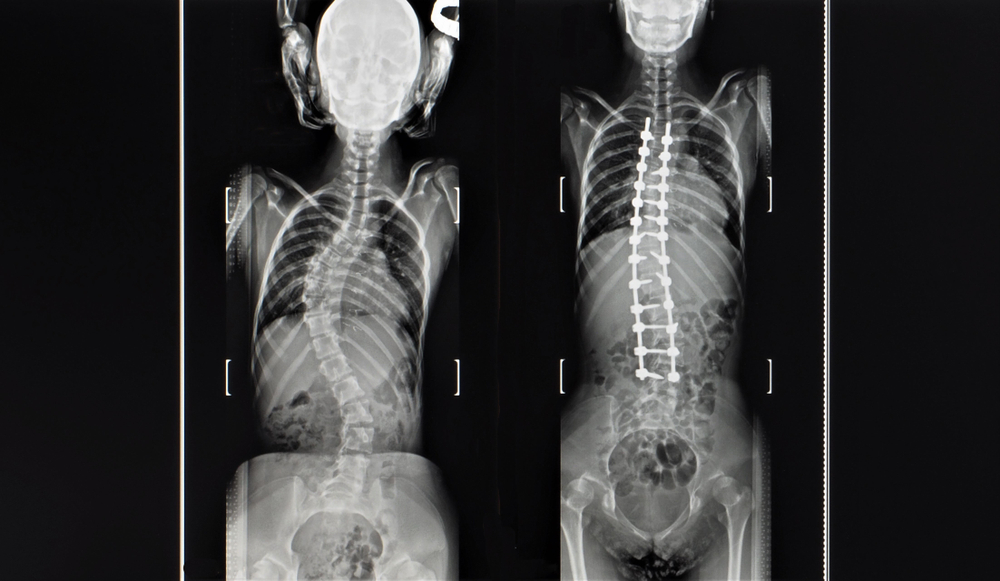

O diagnóstico é confirmado através do exame físico em que o médico pode avaliar o dorso e a altura dos ombros e quadril, assim como com exames de imagem principalmente radiografias panorâmicas da coluna vertebral, perfil e com inclinações laterais e a medida do ângulo da coluna, completa o neurocirurgião.

Dessa forma, geralmente o médico solicita uma radiografia panorâmica da coluna vertebral e avaliação do ângulo, que é uma técnica para medir a deformidade da coluna vertebral. Já em crianças a avaliação é feita e a classificação de Risser é usada para classificar a maturidade esquelética.

- Cirúrgico: Dependendo da progressão da curva, o médico pode indicar o tratamento cirúrgico. Assim, cirurgias de correção são feitas em situações de curvas elevadas, aquelas superiores a 40 graus ou em progressão apesar do tratamento conservador.